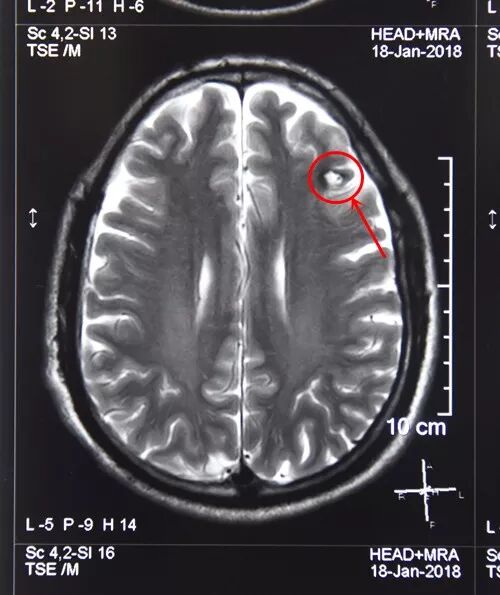

外二科显微手术图片

病人吴某,男,62 岁,因癫痫突然发作且呈癫痫持续状态,入住我院外二科。主管医生梁晓阳立即给予抗癫痫药物治疗,症状缓解后查MRI发现左额叶占位,考虑为海绵状血管瘤,经科室会诊后决定为吴某行左额叶占位切除术。在充分完善术前准备后,3月1日在全麻下采用左额叶弧形小切口,借助显微镜完整切除病灶,取出一直径约2.5cm的血管瘤。目前患者状况良好,神志清楚,正在进一步康复中。

术前核磁共振显示:左额叶占位